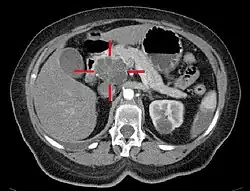

Axial CT image with IV contrast and added color: Cross lines towards top left surround a macrocystic adenocarcinoma of the pancreatic head.

Medical imaging techniques, such as computed tomography (CT scan) and endoscopic ultrasound (EUS) are used both to confirm the diagnosis and to help decide whether the tumor can be surgically removed (its "resectability").[12] On contrast CT scan, pancreatic cancer typically shows a gradually increasing radiocontrast uptake, rather than a fast washout as seen in a normal pancreas or a delayed washout as seen in chronic pancreatitis.[58] Magnetic resonance imaging and positron emission tomography may also be used,[2] and magnetic resonance cholangiopancreatography may be useful in some cases.[34] Abdominal ultrasound is less sensitive and will miss small tumors, but can identify cancers that have spread to the liver and build-up of fluid in the peritoneal cavity (ascites).[12] It may be used for a quick and cheap first examination before other techniques.[59]